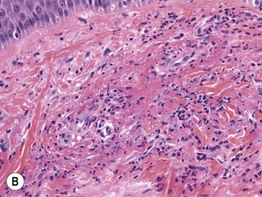

Fig. 1.11 Small vessel vasculitis. A Inflammatory palpable purpura of the leg. B Perivascular and interstitial infiltrate of neutrophils with nuclear dust (leukocytoclasia). Fibrin within the vessel wall and extravasation of erythrocytes is also seen. A, Courtesy, Carlo F. Tomasini, MD; B, Courtesy, Christine Ko, MD.